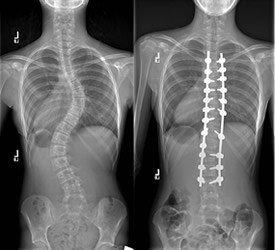

Skolyoz tedavisinde cerrahinin temel amacı, güvenli bir şekilde omurgadaki deformiteyi düzeltmek ve eğriliğin ilerlemesini önlemek için omurgayı dondurmaktır. Skolyotik eğriliğin büyüklüğü cerrahi tedavi kararı için en önemli faktördür. 45-50 derecenin üzerindeki tüm idiyopatik skolyozlar cerrahi tedavi açısından değerlendirilmelidir. Kemik gelişimi tamamlanmış hastalarda 30 derecenin altındaki eğriliğin ilerleme riski yoktur ve eğriliğin şekli ne olursa olsun cerrahi gerektirmez. Fakat Kemik gelişimi tamamlanmış ve 50 dereceyi aşan yada çift eğriliği olan hastalarda eğriliğin zamanla kötüleşme riskinden dolayı cerrahi tedavi gerektirir.

Skolyoz, eğriliğin büyüklüğü ve şiddetine göre ameliyat ya da ameliyat dışı yöntemlerle tedavi edilebilir. Cerrahi dışı yöntemler arasında, eğriliğin ilerleyişini gözlemlemek veya korse kullanmak vardır. Eğer eğrilik, büyüme tamamlandıktan sonra bile ilerlemeye devam edeceği bir noktaya ulaşırsa cerrahi tedavi düşünülebilir.

Skolyozun cerrahi tedavisinde amaç; omurgadaki eğriliğin daha da fazla ilerlemesini engellemek ve omurgayı en güvenli şekilde düzeltmektir. İlerlemenin durdurulması, yaşamın ilerleyen yıllarında ağır skolyozla birlikte olan ciddi sağlık sorunlarını engelleyecektir. Ameliyat sırasında eğrilik, güvenli bir düzeltmenin mümkün olabileceği en yüksek oranda düzeltilir. Bunu yapmak için implantlar, eğriliğin olduğu omurga kısmındaki omurlara tutturulur. Daha sonra çeşitli maniplasyonlarla omurga eğriliği düzeltilir. Ameliyat sonrasında ertesi gün ayağa kaldırılan hastaya günlük yürüme egzersizleri verilir. Hastalarımız 3-7 gün arasında hastanede kalmaktadır.

Bu ameliyatlarda Spinal Navigasyon ve Nöromoniterizasyon cihazları kullanılarak sinirlerde herhangi bir zarar oluşması engellenmektedir.